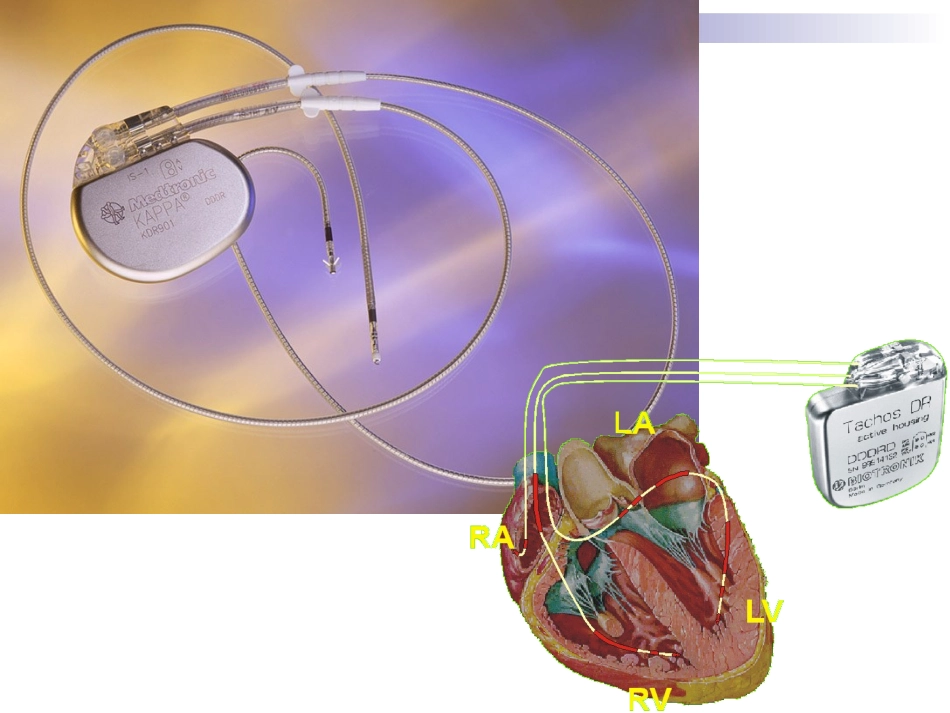

心脏起搏定义人工心脏起搏(artificialcardiacpacing)是通过人工心脏起搏器或程序刺激器发放人造的脉冲电流刺激心脏,以带动心脏搏动的治疗方法。主要用于治疗缓慢心律失常,也用于快速的心律失常和治疗。什么是心脏起搏器?心脏起搏器由脉冲发生器、导线和电极组成。脉冲发生器呈扁圆形,体积非常小,大约有40506毫米,重量约30克。它实际上是一个微型计算机,由高性能电池提供能量。起搏器通常埋植在上胸部的皮下,它的导线通过静脉到达心脏,导线顶端的电极固定在心脏的内侧面心肌上。起搏器工作时,脉冲发生器发出的电脉冲,经导线、电极传到心肌,心肌感受到电脉冲刺激产生收缩。同时,起搏器电极也将心脏的电活动收集起来存入脉冲发生器内的芯片内,以便进行分析。人工心脏起搏器工作原理:监测...